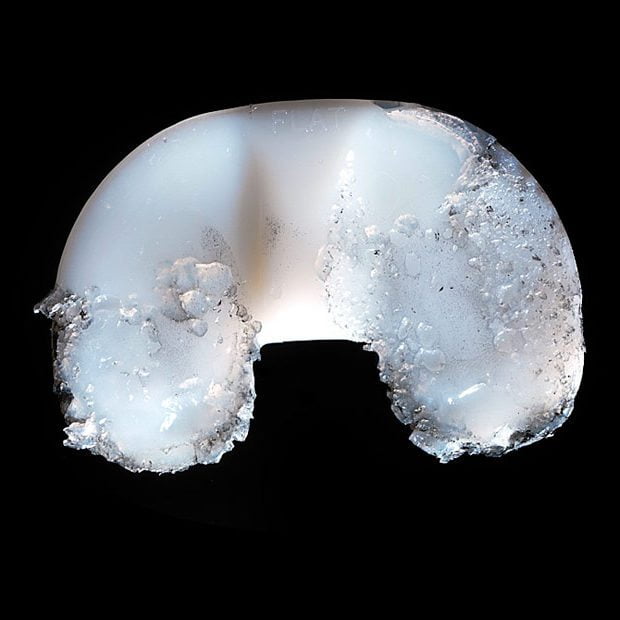

- Пластиковая прокладка. Располагается между большеберцовой и бедренной частью. Изготавливается из пластика (полиэтилена). Эта гибкая распорка обеспечивает гладкую, скользящую поверхность для обновленного коленного сустава, позволяет ему изгибаться и гнуться.

Полиэтилен с высокой молекулярной массой – распространенный материал для изготовления пластиковых компонентов. Его широкое распространение объясняется способностью плавного скольжения в пределах механического соединения, имитирующего естественные движения коленного сустава.